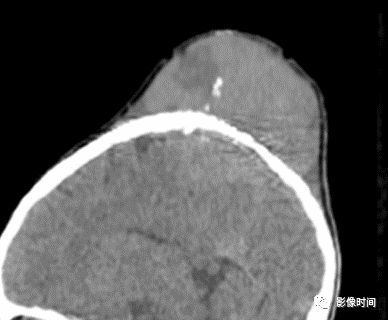

(二)膨胀性破坏  膨胀性破坏是地图样破坏的特殊形式,影像学表现为骨质破坏区骨膨胀,周围可见不同程度扩张的骨壳(图 5、图 6、图 7、图 8)。

膨胀性破坏是由于肿瘤从骨皮质内面破坏,骨外膜增生形成新生骨造成膨胀的。

引起膨胀性破坏见于大多数良性肿瘤和肿瘤样病变如单纯性骨囊肿,动脉瘤样骨囊肿、内生软骨瘤和软骨粘液纤维瘤等,少数也可见于恶性肿瘤如转移瘤、骨髓瘤等。

图 5  膨胀性破坏:动脉瘤样骨囊肿

图 6  膨胀性破坏:骨巨细胞瘤

图 7  膨胀性破坏:内生软骨瘤

图 8  膨胀性破坏:软骨粘液样纤维瘤